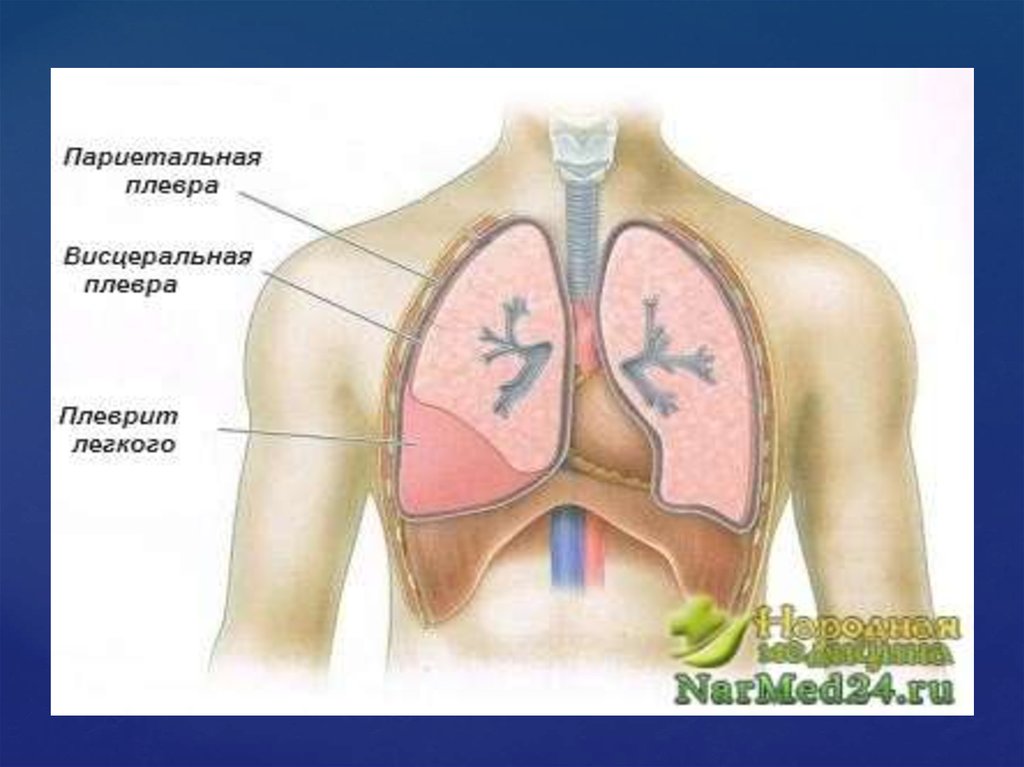

Симптомы и причины скопления воды в легких